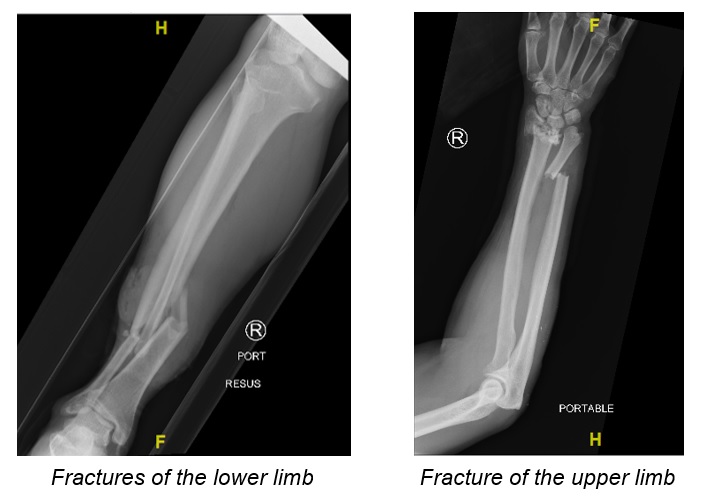

Common types of injuries to the extremities and pelvis include mangled limbs, bone fractures and damaged blood vessels.